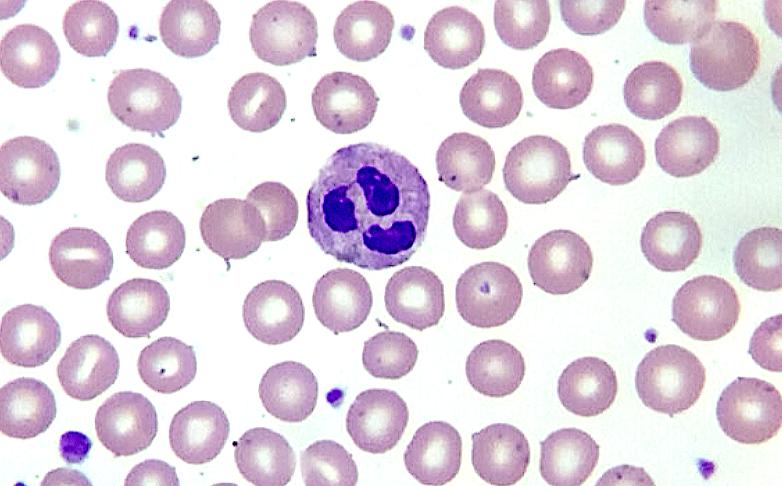

Hematology

Precise automated WBC differential counts with advanced morphology recognition in blood and bone marrow smears